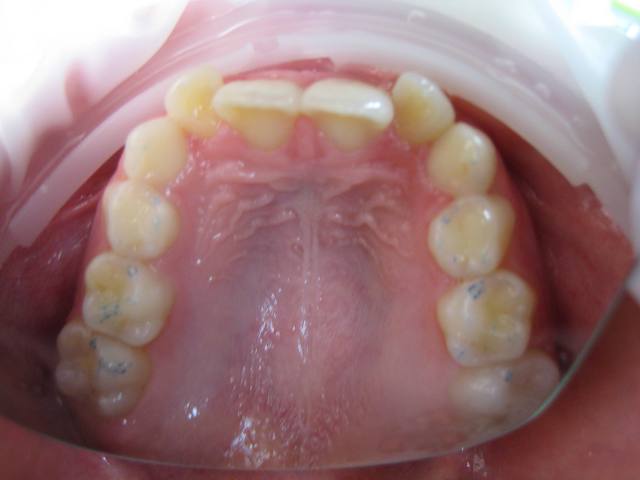

Je suis entrain de faire une observation clinique d'une patiente de 10 ans.

Elle présente une linguo-version et une égression des incisives maxillaires et mandibulaires. Le truc c'est que les racines de 11 et 21 semblent bien positonnées sur la télé de profil, alors que les faces vestibulaires sont très lingualées.

Photos endobuccales  1  ap7xrd - Eugenol

je crois que la forme très bombée de la couronne de centrale sur la radio, et qu'on ne voit pas sur les photos, est due à la superposition des quartes inciives. Quand au traitement, il s'agit d'un traitement classique d'un cas de classeII div 2.

Attention quand même aux racines des centralesavant de commencer, une retroalvéolaire pourrait être utile.